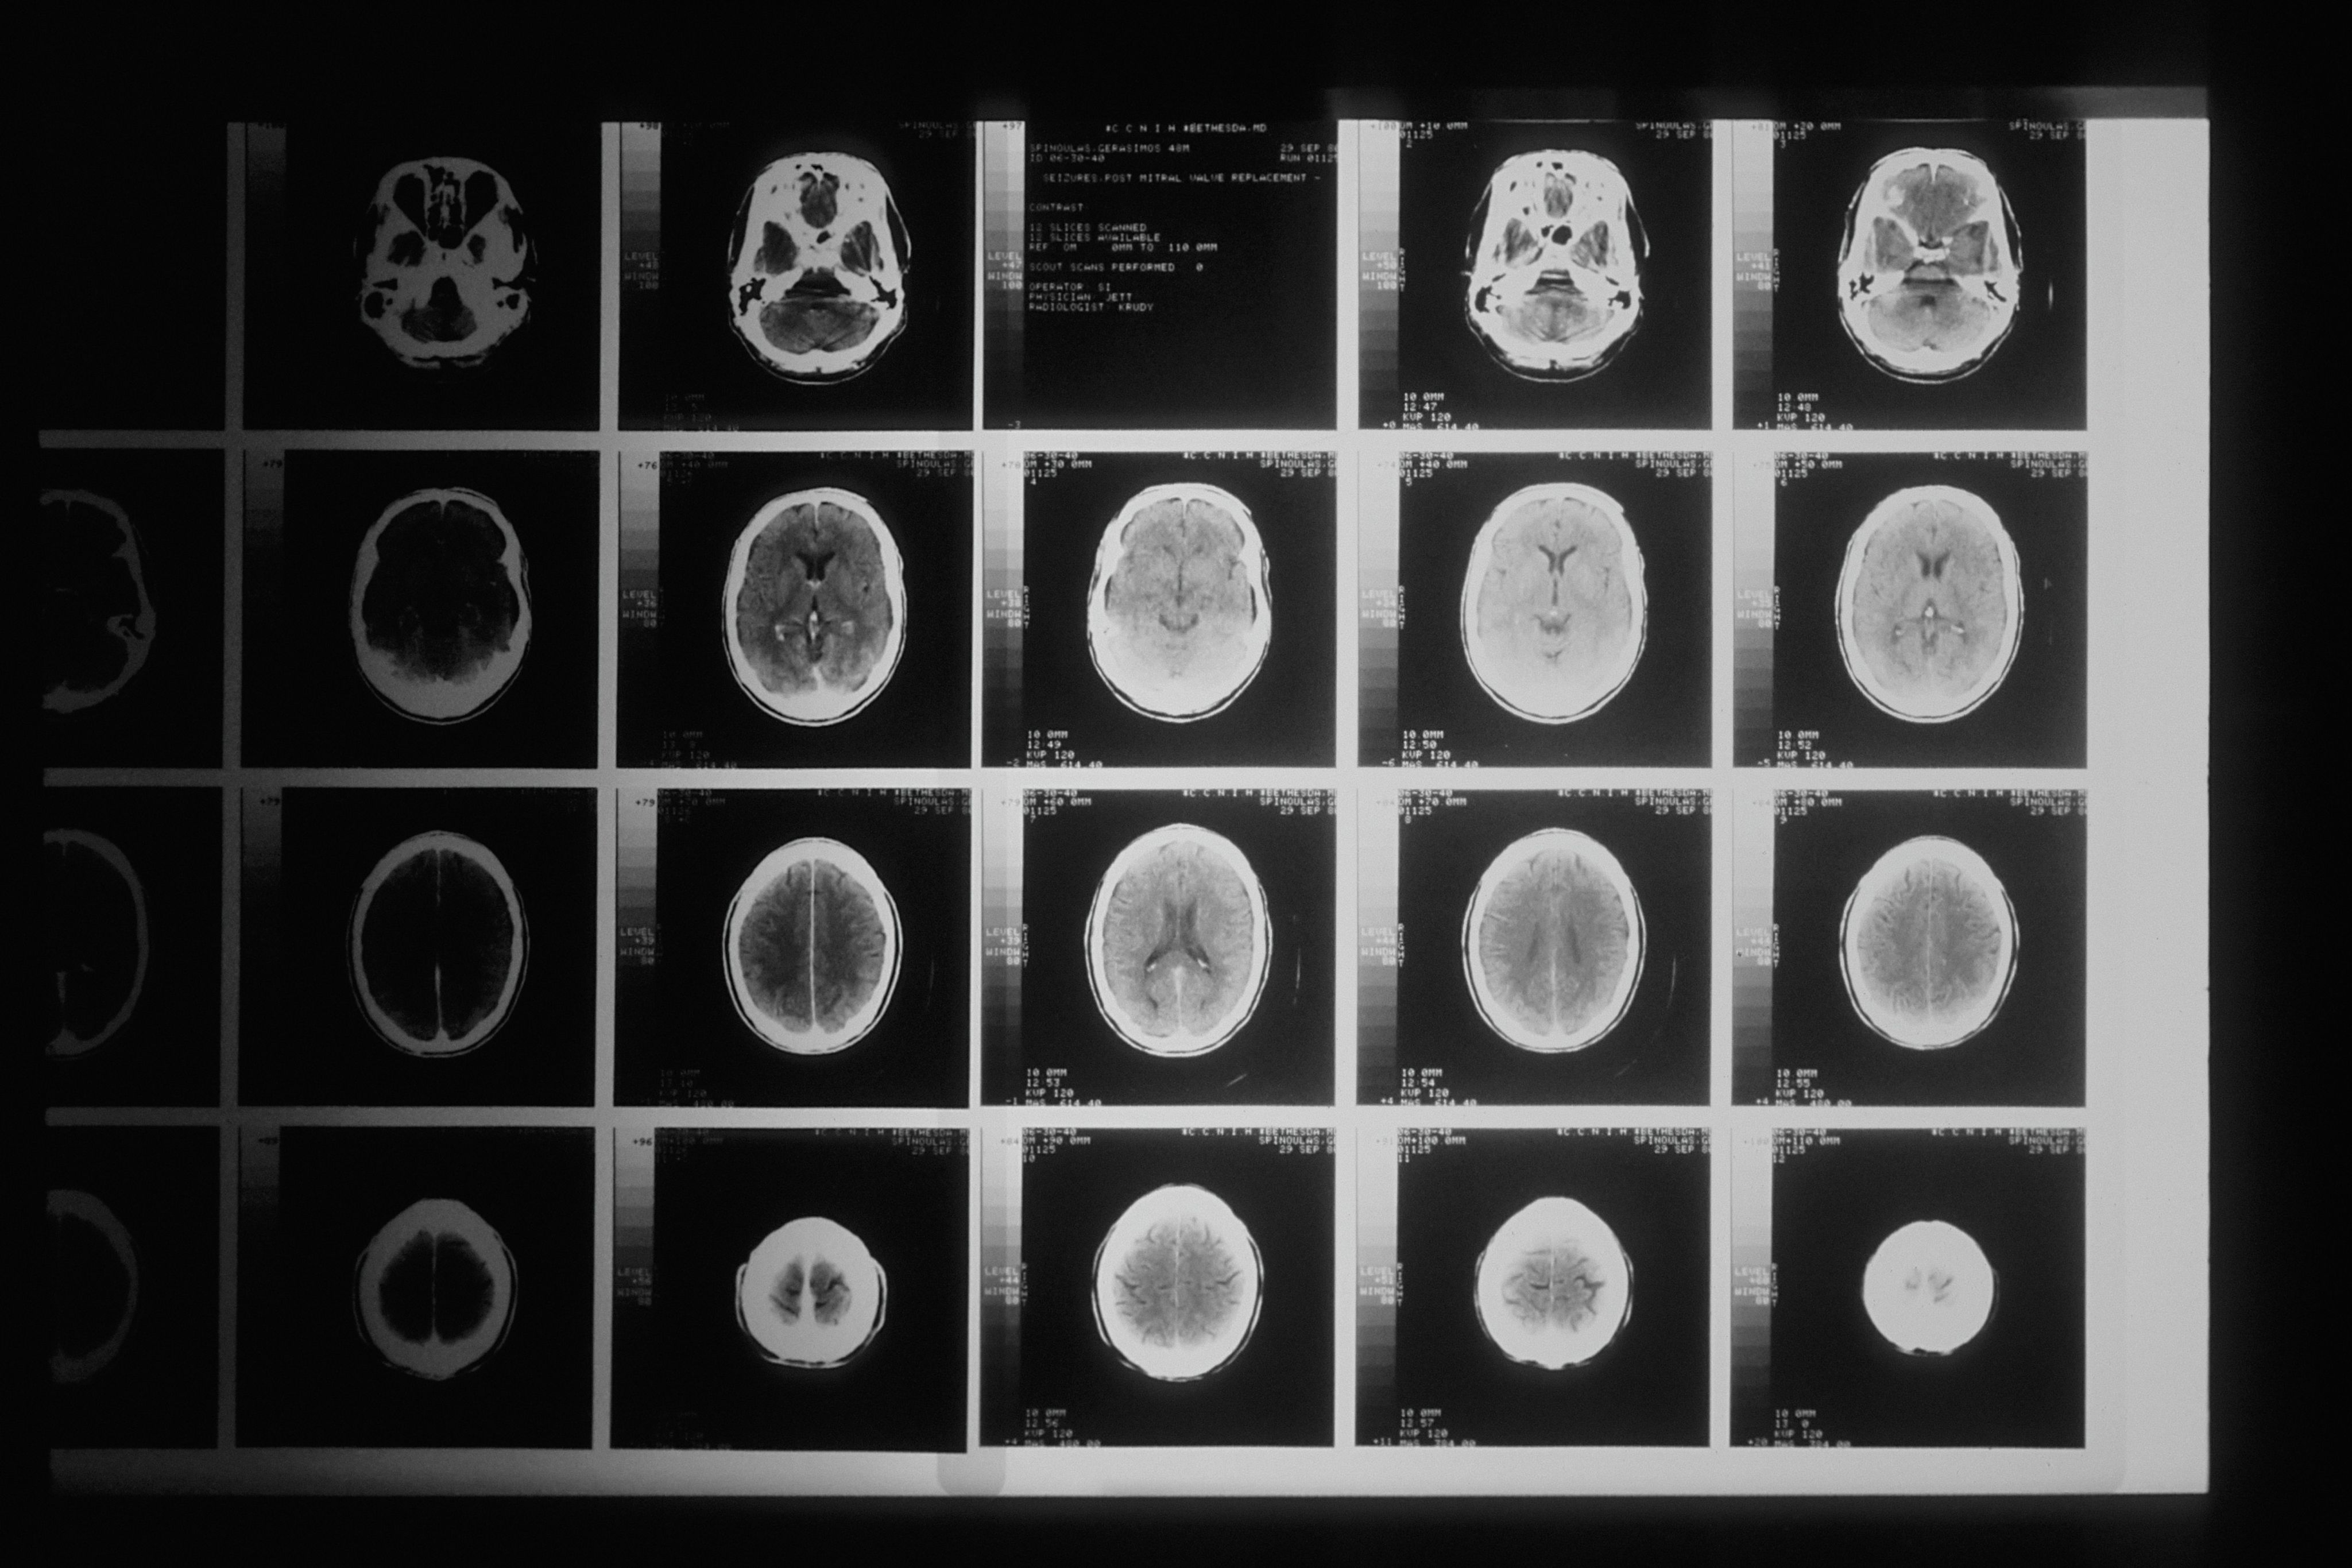

Jackson’s treatment includes a vagus nerve stimulation (VNS) device, a small implant placed in the chest and connected to the vagus nerve in the neck. The device sends regular electrical signals to the brain to help reduce seizure frequency and intensity.

When a seizure begins, a magnet can be used to manually activate the device, delivering an extra pulse that may shorten or stop the episode. While the VNS does not cure epilepsy, it provides an added layer of control in a condition defined by unpredictability.

Jackson's husband, Darrien, has been trained to use a VNS device, which is implanted in her chest to help stop seizures. Jackson also has a responsive neurostimulation (RNS) device, which monitors her brain activity and requires her to upload data.